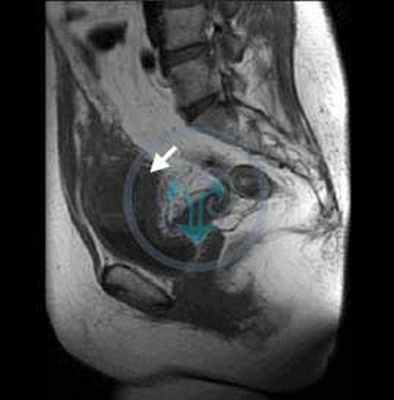

Диагноз устанавливается на основании УЗИ (рис. 5.35), цистографии (рис. 5.36) и цистоскопии (рис. 20, см. цв. вклейку).

Рис. 5.35. Трансабдоминальная сонограмма. Дивертикул (1) мочевого пузыря (2)